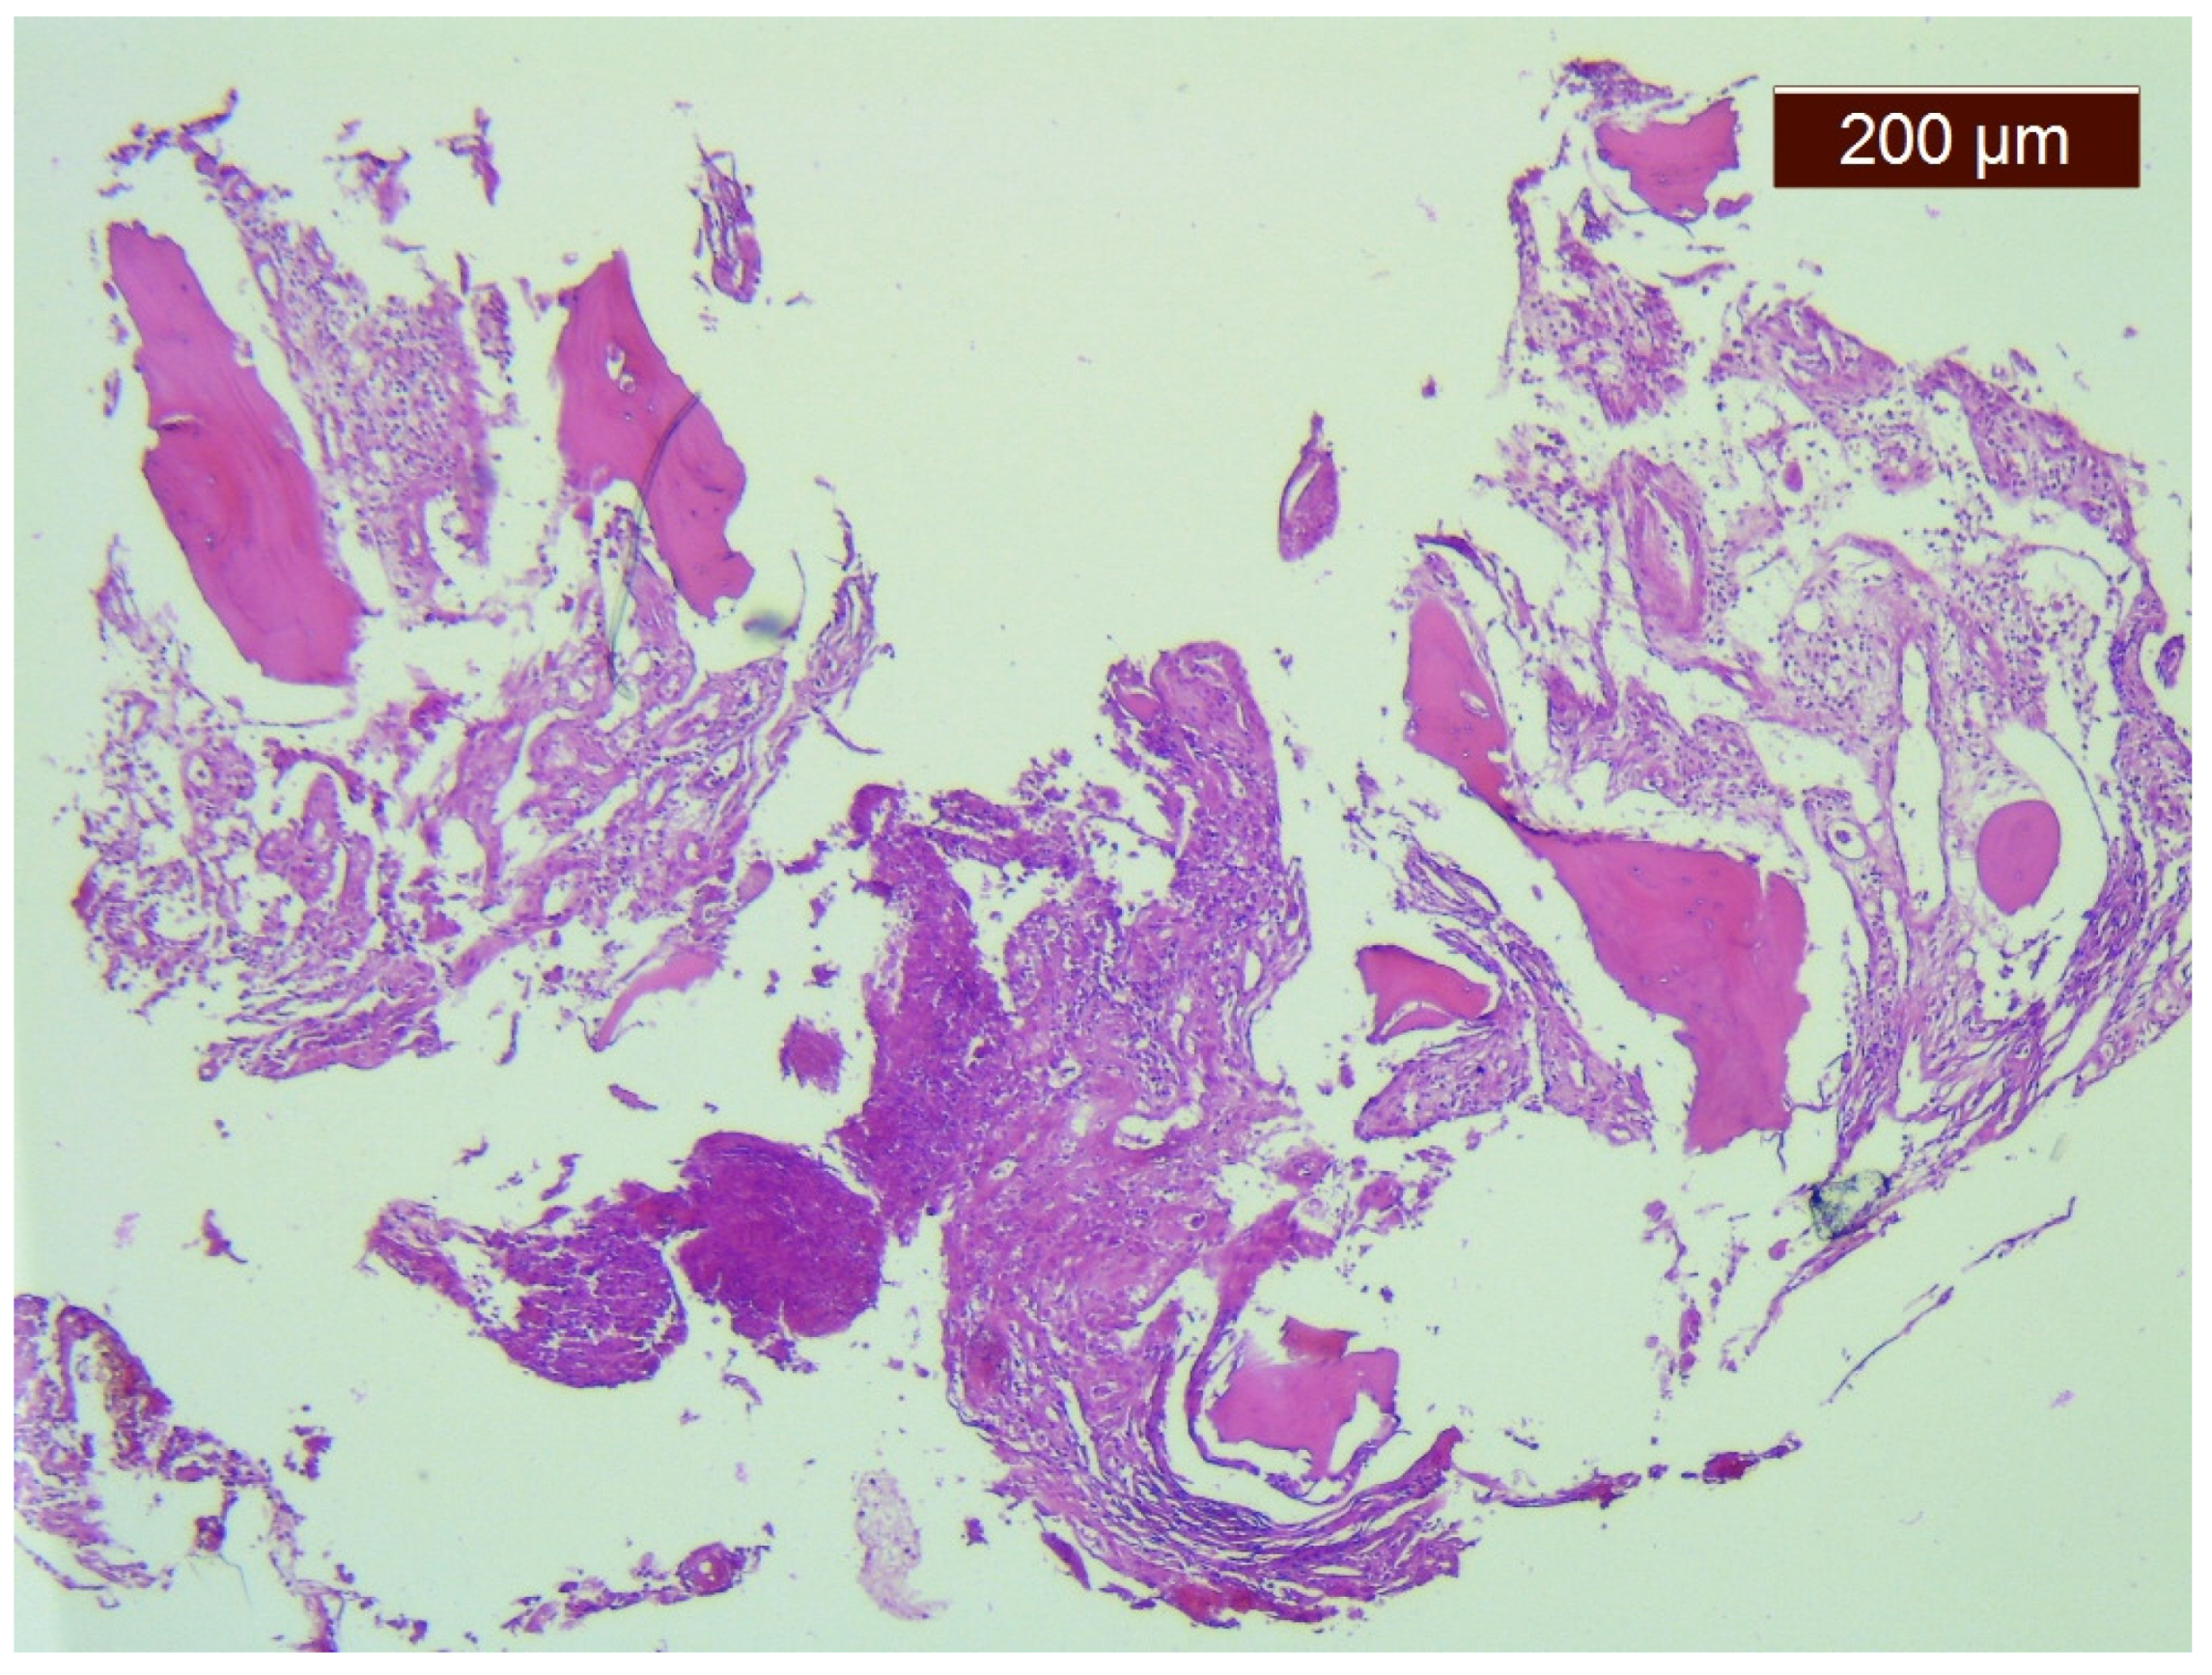

2. Case Report

| Month I | C7 corpectomy and reconstruction with autologous graft from the iliac crest, macroscopic resection of the posterior arches C7-T1 and fixation with C4-C5-T3-T4 cervico-thoracic hybrid system |

| Month III | Ablation of osteosynthesis material and bone graft and T1 corpectomy, reconstruction with C6-T1 mesh fixed with proximal and distal screw |

| Month IX | Ablation of damaged osteosynthesis material mesh C6-T1, ablation of thoracic screws, and introduction of bilateral T3, T4, and T5 screws |